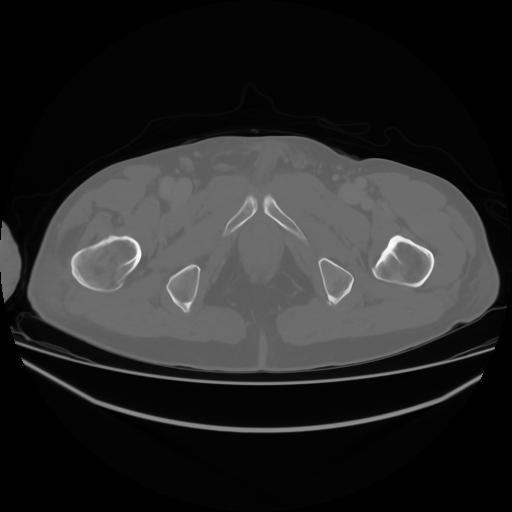

4 CUERPO,CE,Axial,3.0,CUERPO,,